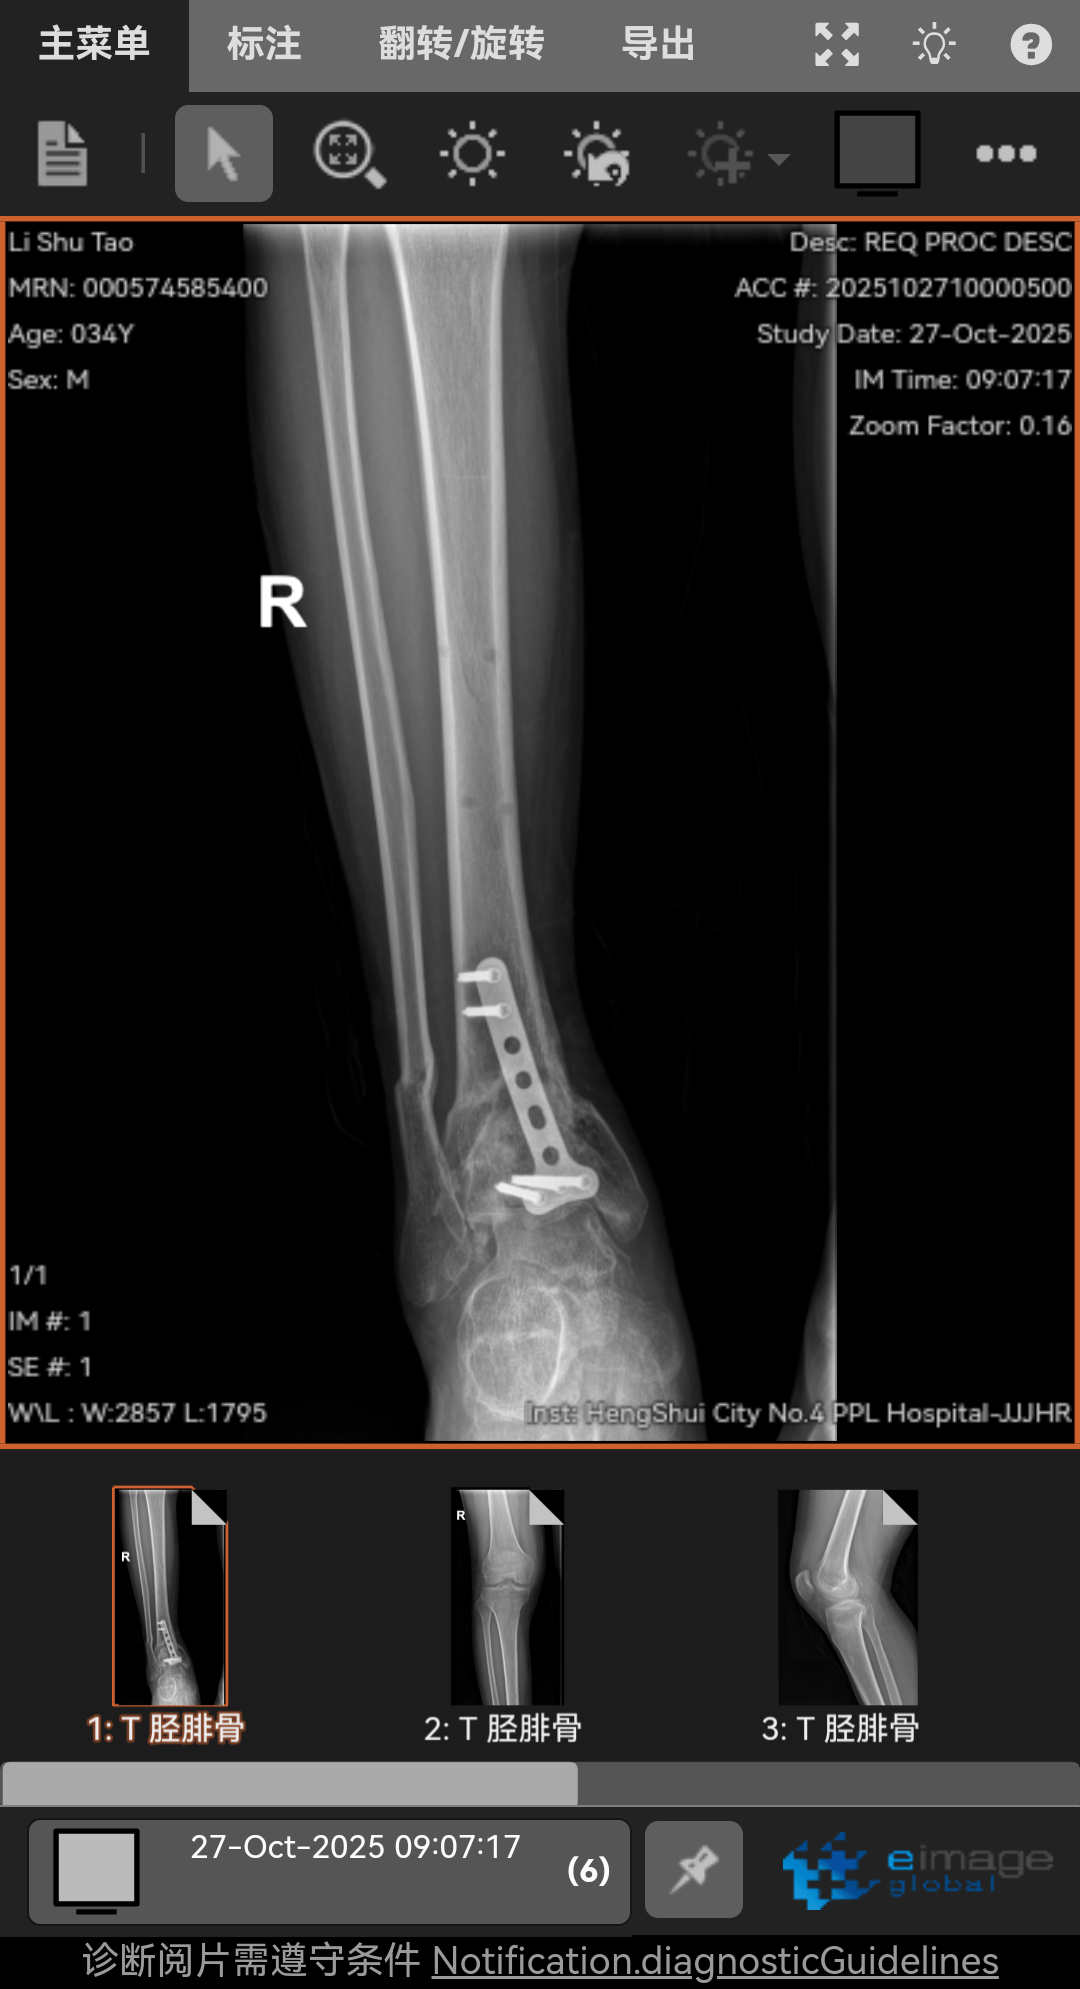

高坠骨折,6个月了,脚底板麻木,按压有刺痛,我是汗脚现在脚底板干燥,怎么办呢?走路腿特别沉重脚踝活动还不行,膝盖伸不直有点积液,怎么办呢!求求兄弟姐妹你们了。